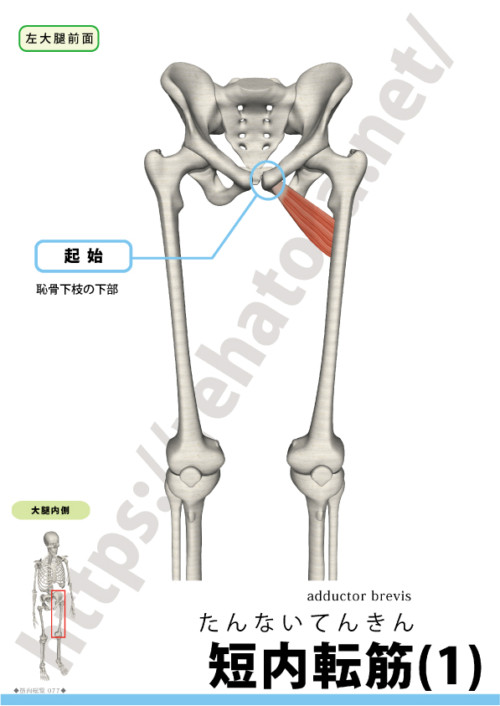

短内転筋の概要

短内転筋は大内転筋の前方を走る内転群の中間層で、表層を恥骨筋・長内転筋に覆われます。主作用は股関節内転。肢位によってわずかな屈曲・内旋にも寄与します(とくに外転位/屈曲位で内旋成分が出やすい)。

| 起始 | 恥骨下枝(下方) |